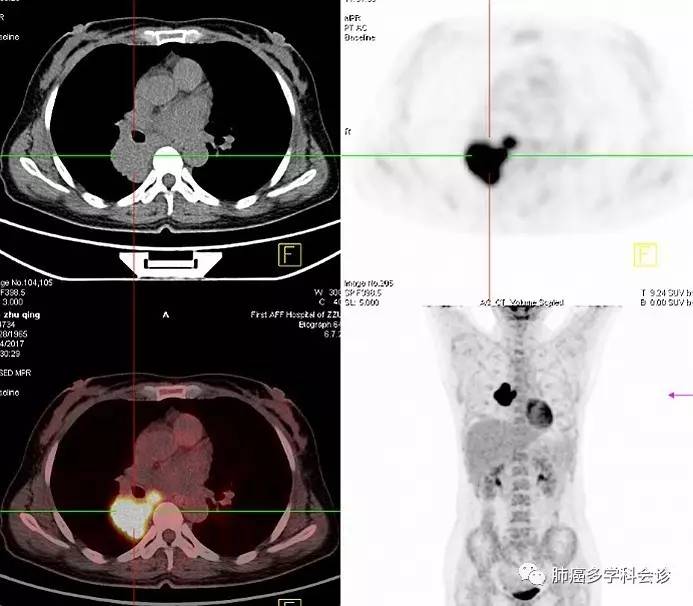

微信图片_20170717104646.jpg微信图片_20170717104650.jpg肿瘤组织NGS基因检测:ERBB2(HER2)20外显子非移码插入性突变,丰度25.3%。

2017.05 复查 CT:右肺病灶较前稍增大,腰 2、4 椎体内高密度影,右肺中下叶多发小结节。“培美曲塞 + 顺铂”化疗 2 周期后病灶都有不同程度减小,腰4椎体病变范围较前显著(成骨加强是治疗有效的标志之一)。目前完成 3个周期化疗,升高的血清肿瘤标志物 CEA 和 CA125 均明显下降。

疗效评价:部分缓解(PR)。